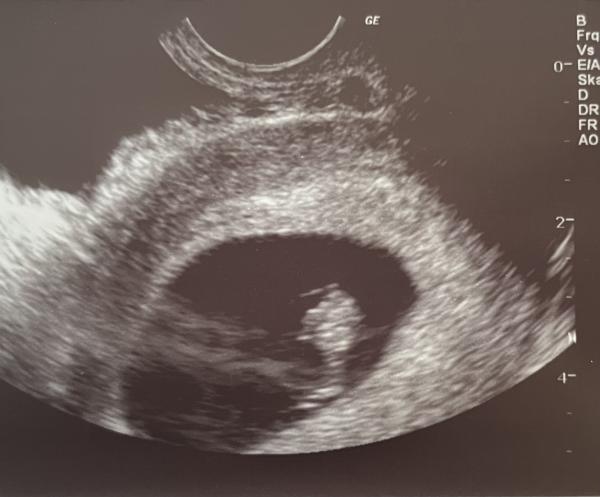

Hallo ihr lieben 🥰  wer kennt sich aus? Das Bild ist bei 7 + 5 vaginal geschallt worden ☺️  Liebe Grüße und danke an alle ☺️

Bild zu Ramzi Methode - Schwanger - wer noch? Rund um die Schwangerschaft

Guten Morgen Mina, ich bin mir nicht ganz sicher, ob das wirklich das "richtige" Schnittbild für die Rami Methode ist. Ist es von Oben gesehen (also die Richtige Schnittebene und nicht vom Arzt ein gespiegeltes Bild) würde ich auf einen Jungen Tippen, da die Hellere Struktur (evtl. die Placenta Anlage) rechts liegt.  Liebe Grüße und besinnliche Feiertage  Cleo